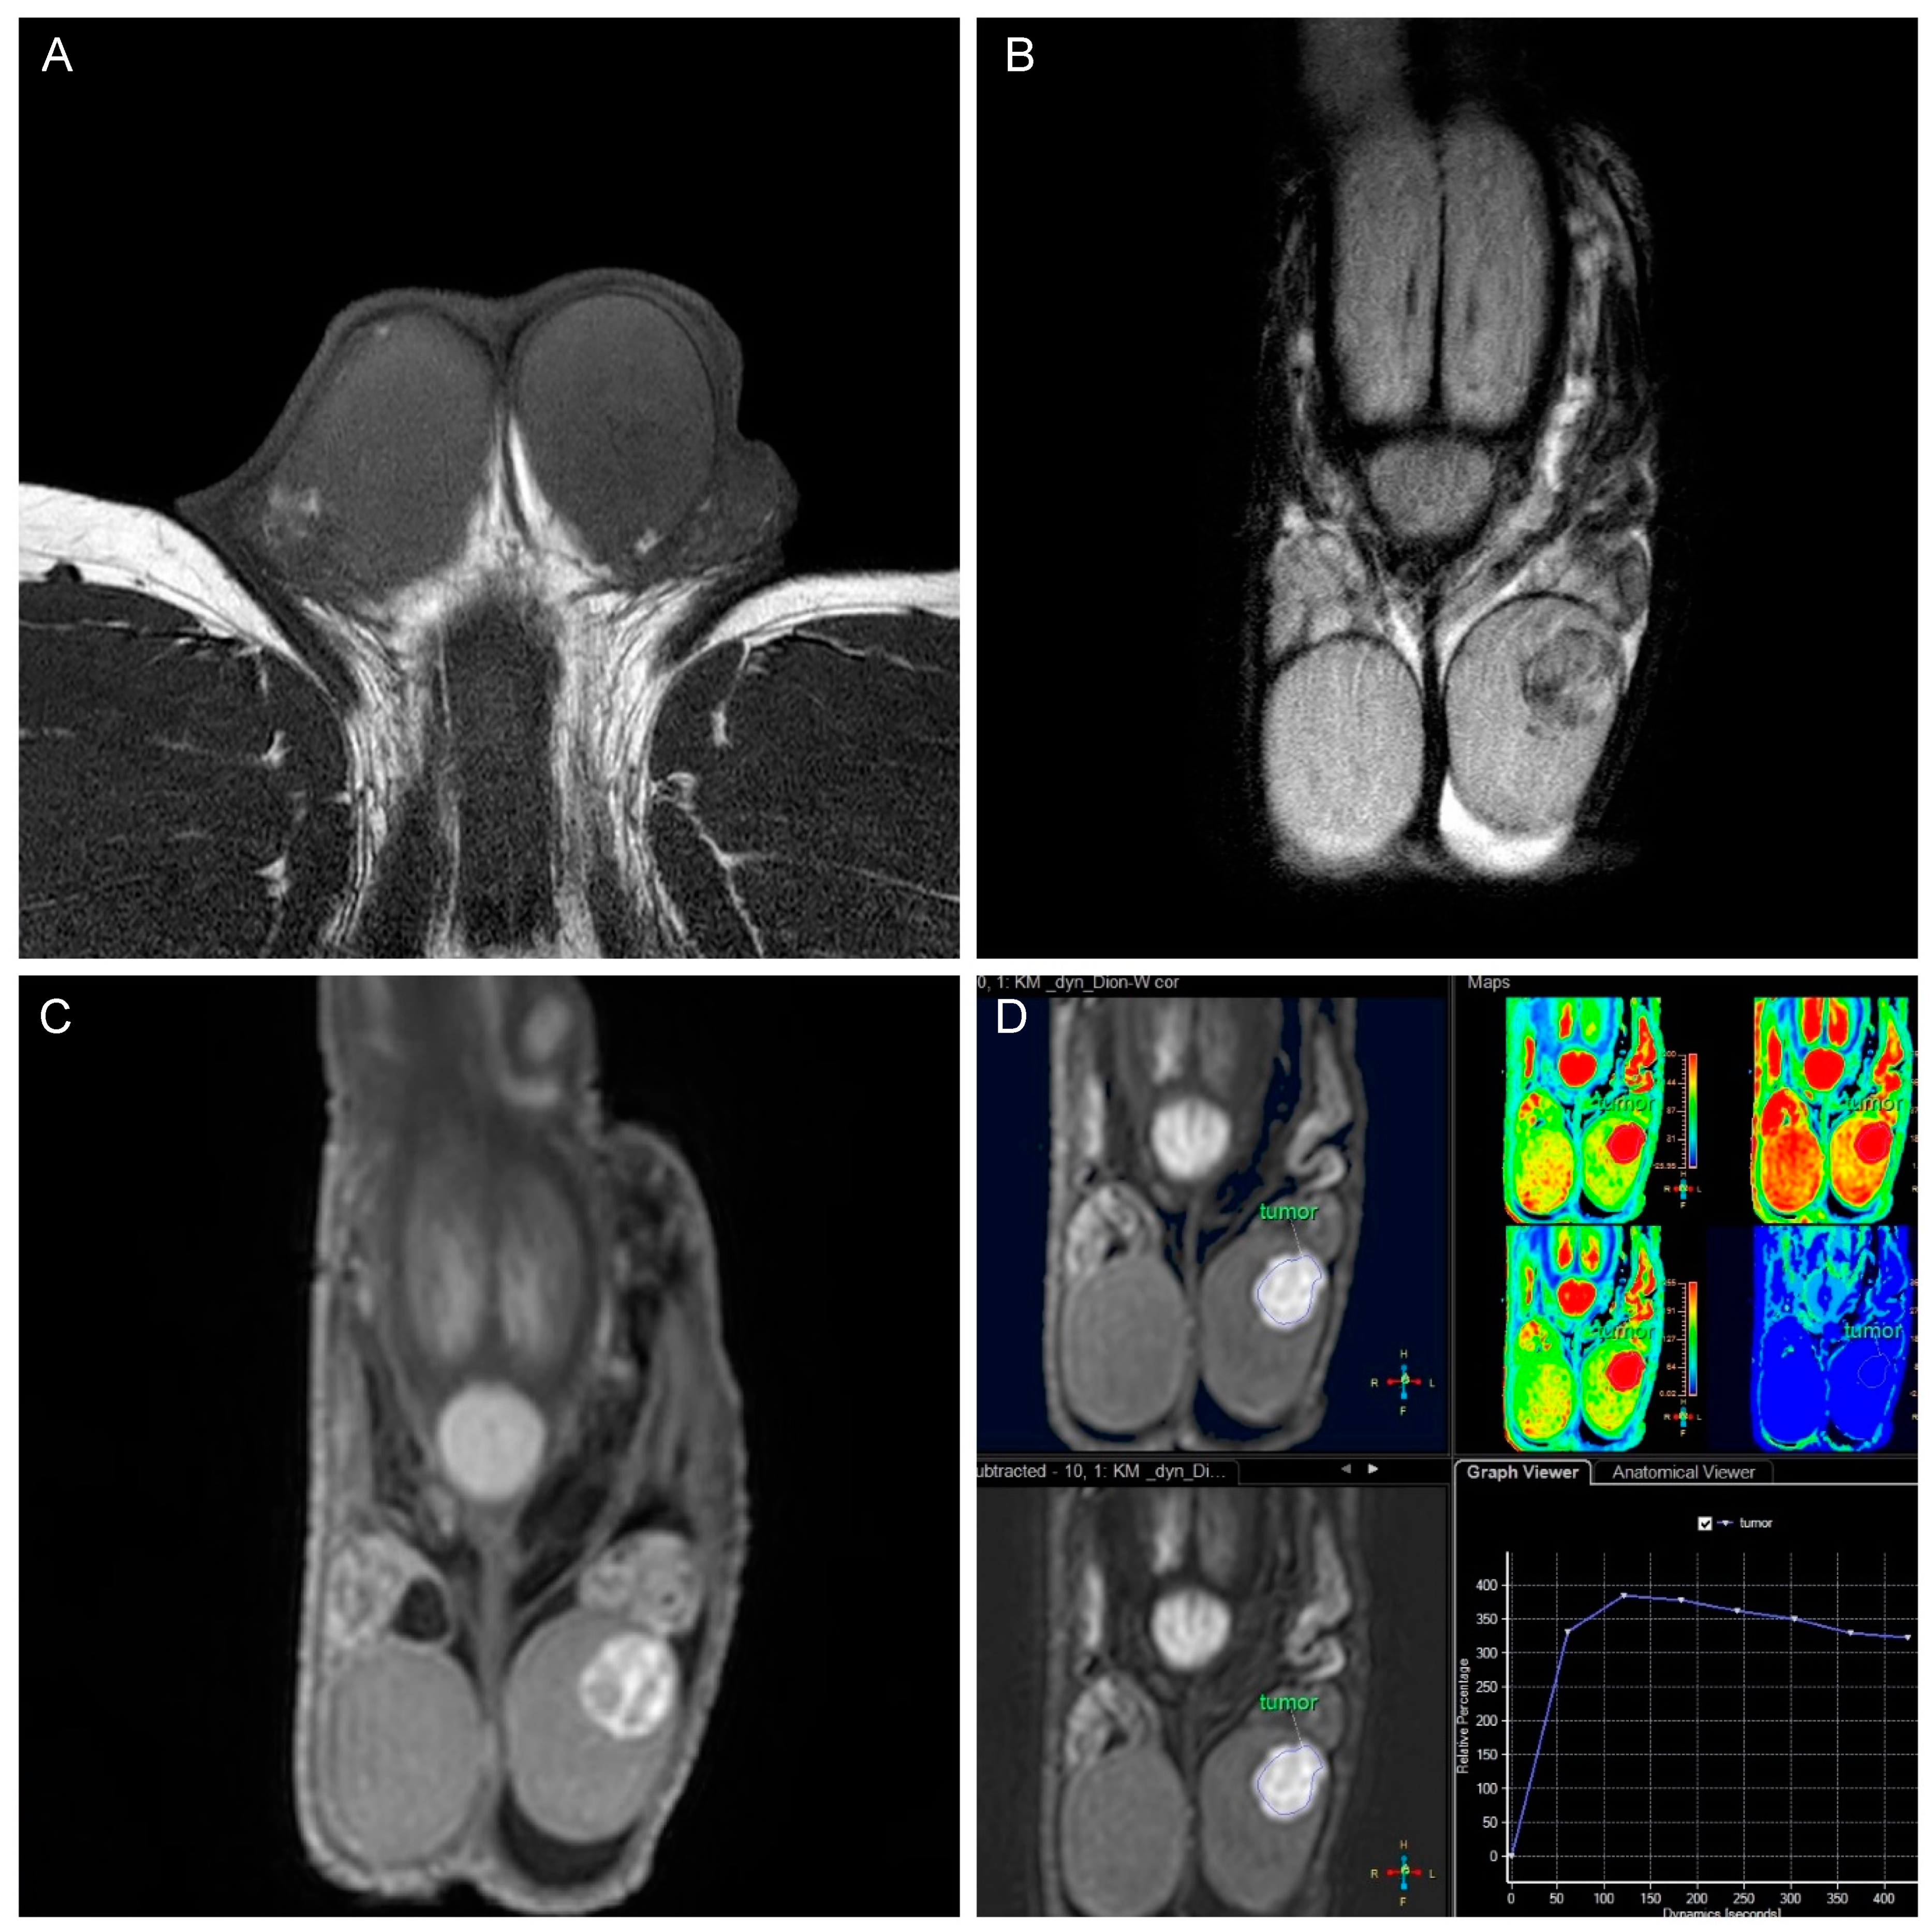

| Type of contrast enhancement (compare [20]) | n absence of enhancement/Type 0 curve (%) | 3 (25.0) | 1 (2.9) | p = 0.025 * |

| n Type I curve (%) | 2 (16.7) | 10 (28.6) | ||

| n Type II curve (%) | 2 (16.7) | 17 (48.6) | ||

| n Type III curve (%) | 5 (41.7) | 7 (20.0) | ||

| Pattern of contrast enhancement | n homogenous (%) | 6 (66.7) | 5 (14.3) | p = 0.005 ** |

| n heterogenous (%) | 2 (22.2) | 22 (62.9) | ||

| n rim-like (%) | 1 (11.1) | 8 (22.9) | ||

| T1 signal | n predominantly low (%) | 2 (16.7) | 3 (8.6) | 0.387 1 |

| n isointense (%) | 10 (83.3) | 30 (85.7) | ||

| n predominantly high (%) | 0 (0) | 2 (5.7) | ||

| T2 signal | n predominantly low (%) | 6 (50.0) | 25 (71.4) | 0.148 2 |

| n isointense (%) | 1 (8.3) | 5 (14.3) | ||

| n predominantly high (%) | 4 (33.3) | 5 (14.3) | ||

| n no signal (%) | 1 (8.3) | 0 (0) | ||

| Presence of enhancing intra-tumoral septa | n Yes (%) | 2 (16.7) | 17 (48.6) | p = 0.087 3 |

| n No (%) | 10 (83.3) | 18 (51.4) | ||

| Presence of areas of hemorrhage (= T1 hyperintensity) | n Yes (%) | 0 (0) | 5 (14.3) | p = 0.309 3 |

| n No (%) | 12 (100) | 30 (85.7) | ||

| Presence of areas of necrosis (= T2 hyperintensity) | n Yes (%) | 2 (16.7) | 9 (25.7) | p = 0.703 3 |

| n No (%) | 10 (83.3) | 26 (74.3) | ||

| Presence of calcification | n Yes (%) | 1 (8.3) | 4 (11.4) | p > 0.999 3 |

| n No (%) | 11 (91.7) | 31 (88.6) | ||

| Presence of ipsilateral hydrocele | n Yes (%) | 10 (83.3) | 19 (54.3) | p = 0.095 3 |

| n No (%) | 2 (16.7) | 16 (45.7) | ||

| Smooth tumor margins | n Yes (%) | 11 (91.7) | 22 (62.9) | p = 0.077 3 |

| n No (%) | 1 (8.3) | 13 (37.1) | ||